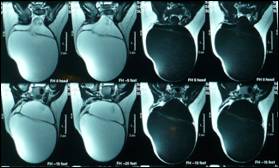

Figure

4: Another cyst inside the major cyst- the terminal myelocystocele.